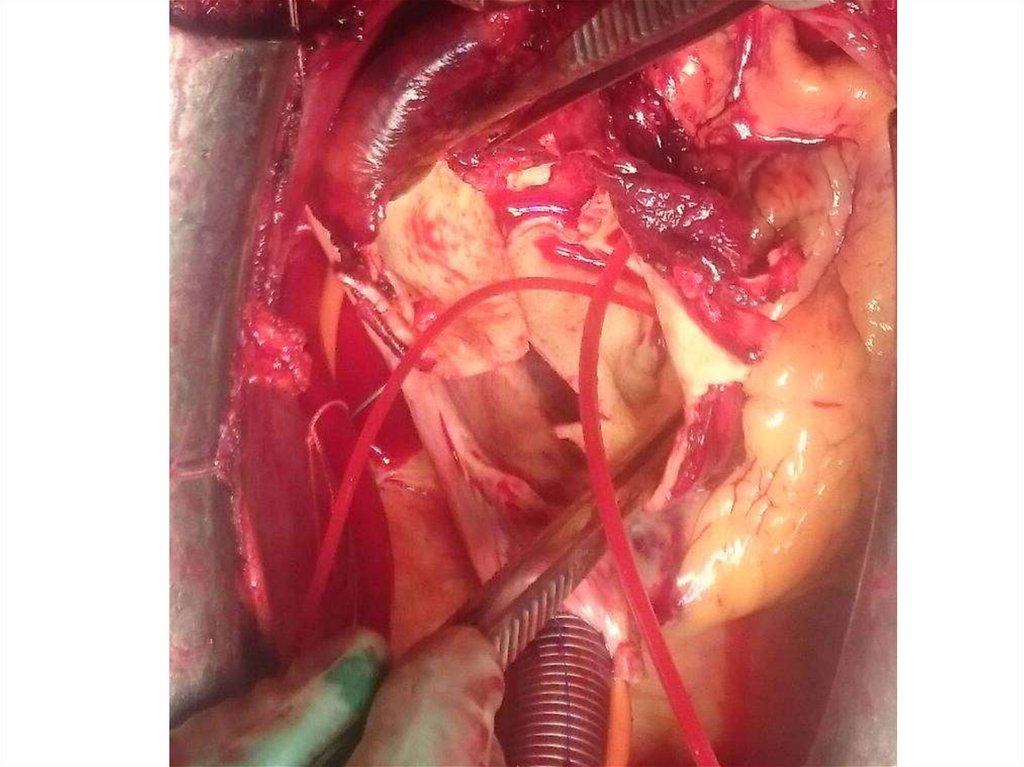

4. Операция 21.03.18:

• Протезирование восходящей аорты клапансодержащим

кондуитом (операция Бенталла – де Боно)

5. Операция (продолжение)

• В перикарде 150 мл темной крови.

• Восходящая аорта расширена, расслоена.

• Все синусы значительно расширены (до

6см)

• Двустворчатый АоК.

• Кардиоплегия по Дель-Нидо.

• Гипотермическая перфузия (28оС)

• Гипотермический ЦА (2 мин)

• ПАо – 87мин, время ИК – 132 мин.